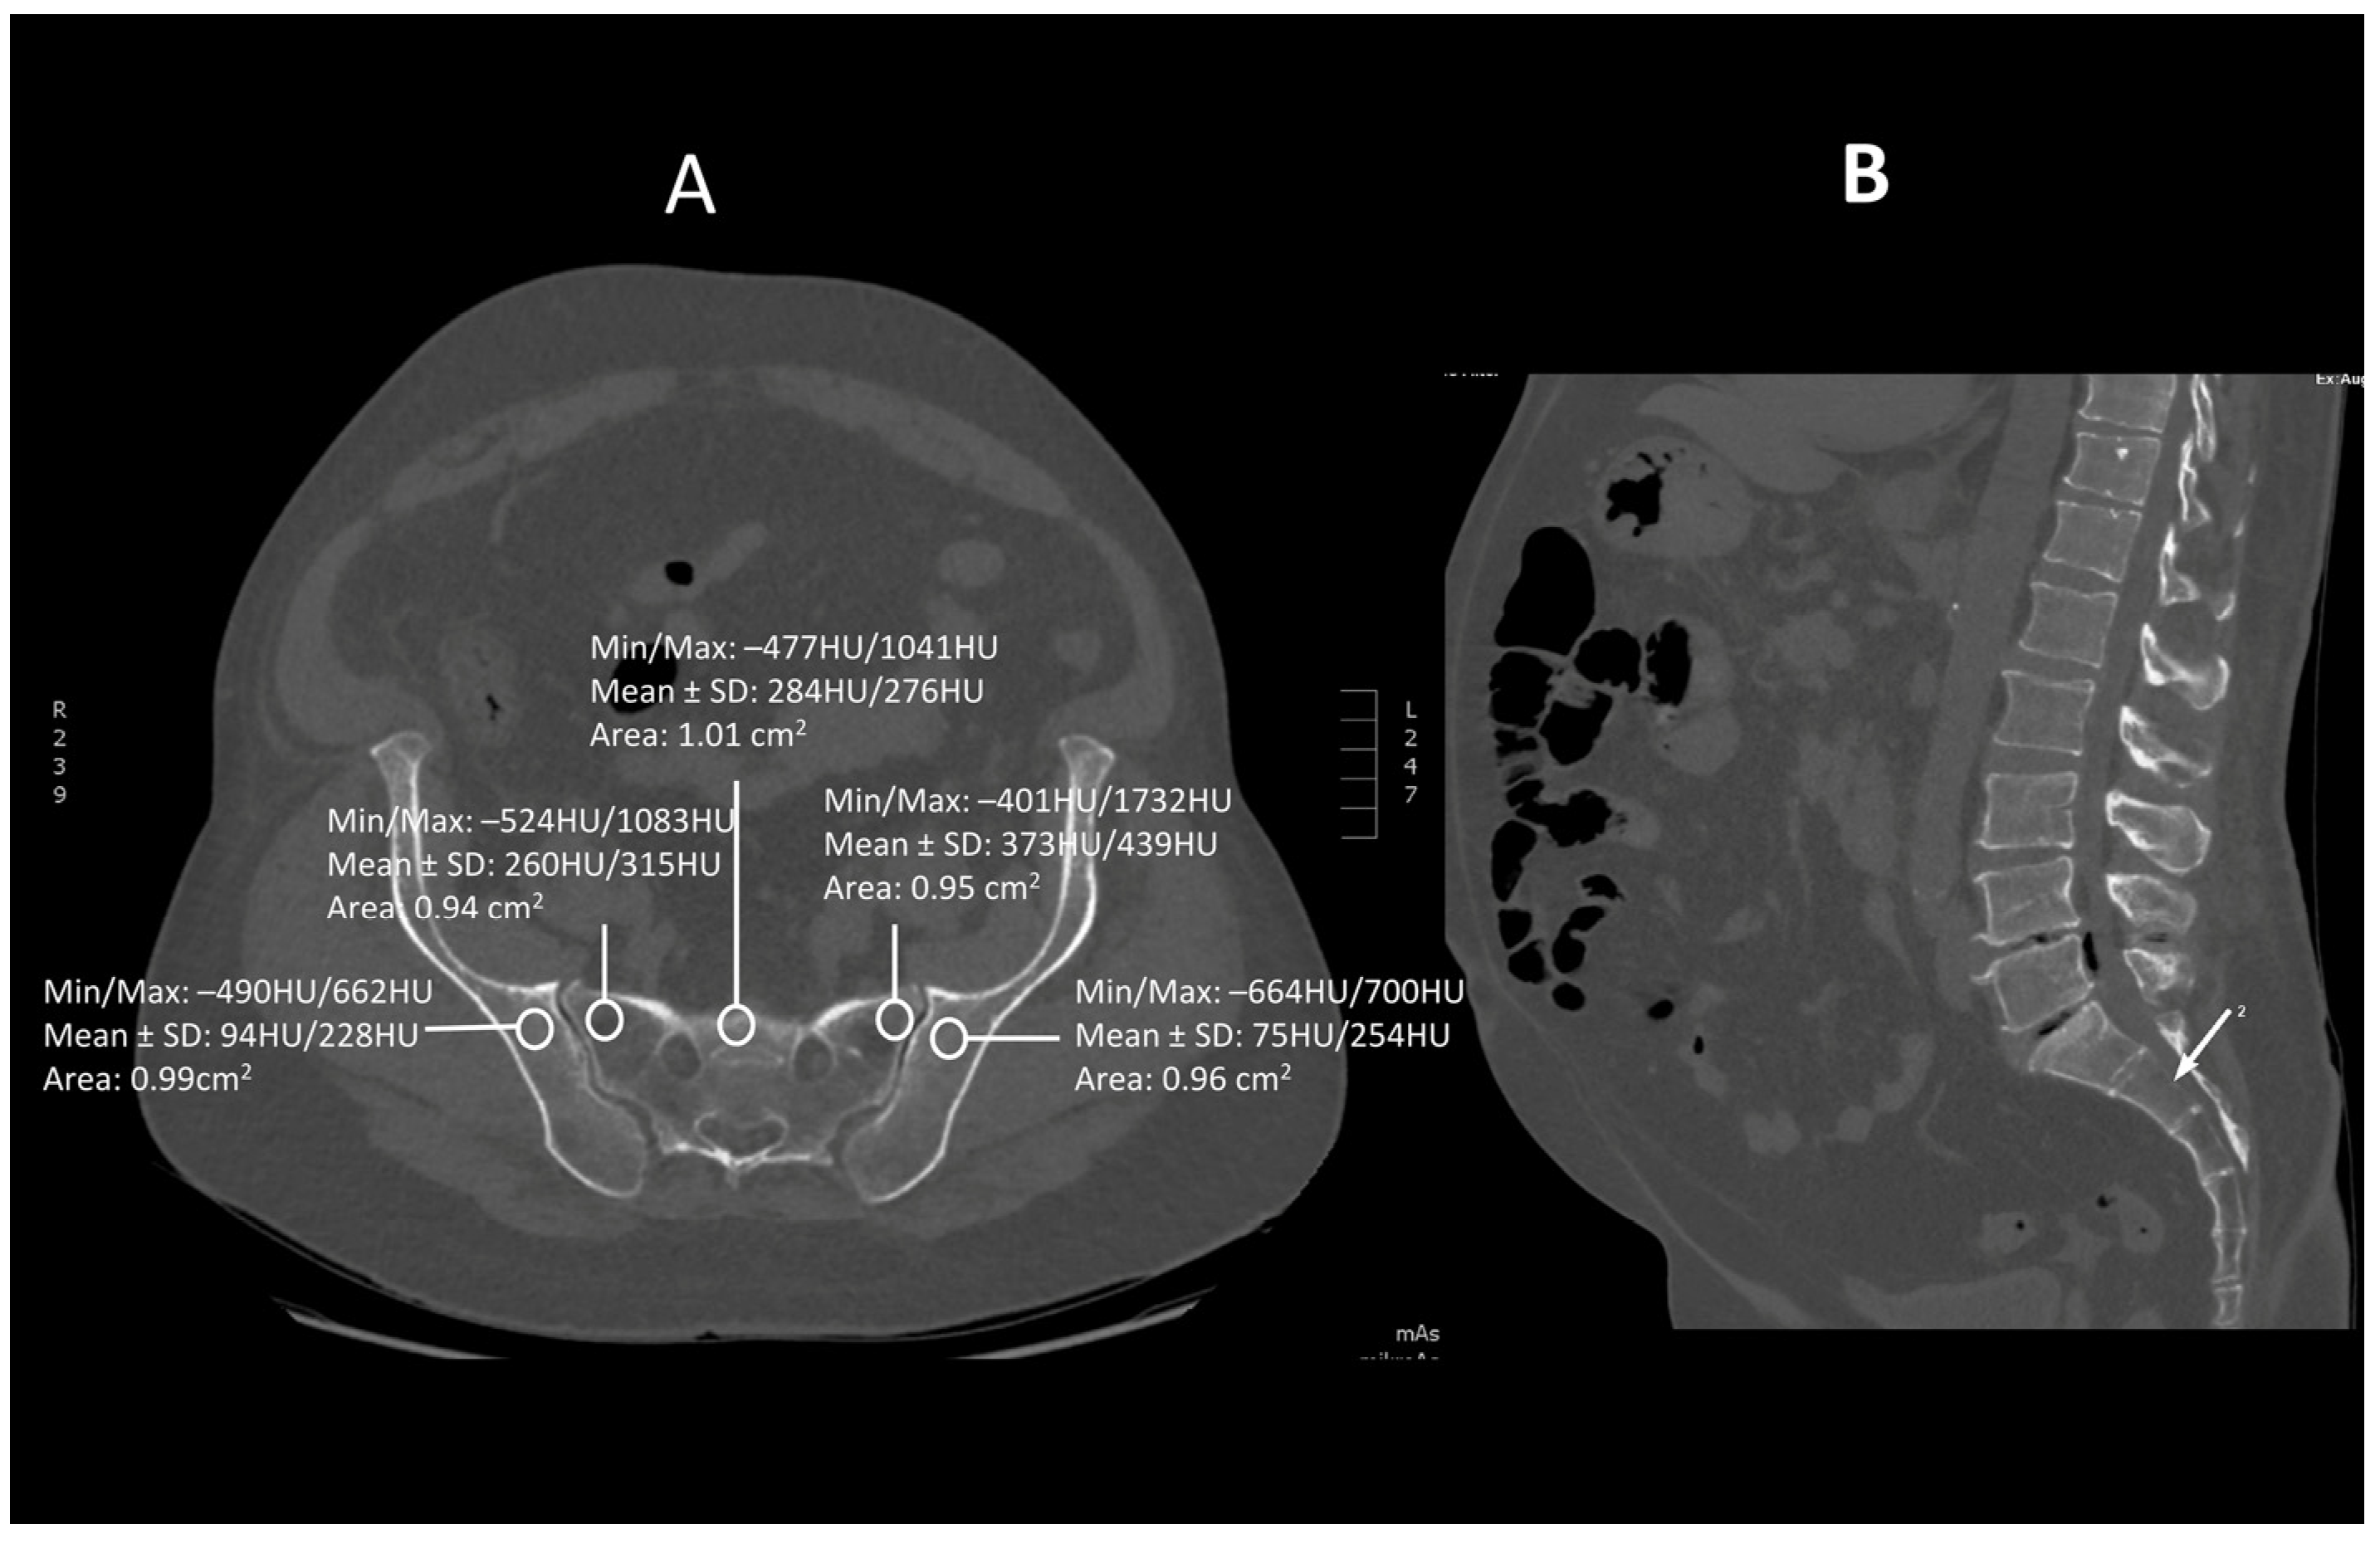

Figure 2.

A transverse (A) and saggital (B) projection of CT scan in level S2. A circular region of interest (ROI) ranging from 0.8 to 1.2 cm2 has been placed at the ala of the ilium, the wing of the sacrum and the tbody of sacral vertebra 2.

Images were viewed using the bone algorithm default windows. The investigator first determined axial images in levels of mid-lengths of bodies of sacral vertebrae 1, 2 and 3 that afterward were confirmed by coronal and sagittal reconstructions (Figure 1, Figure 2 and Figure 3). The volumetric bone density expressed in HU values was measured in sacral levels of S1, S2 and S3. Apart from the bodies of sacral vertebrae S1–S3, the measurements involved the ala of the ilium in the vicinity of the sacroiliac joint and the wing of the sacrum. All the measurements were performed on the pathway of presumptive iliosacral screws to stabilize the sacroiliac joint.

In order to standardize measurements while accounting for normal anatomic variations and optimum iliosacral screw trajectories—so as to avoid injuries of neurovascular structures—standardized circular voxel regions of interest (ROIs) were drawn (Figure 1, Figure 2 and Figure 3) [12]. As presented in the former studies, these ROIs were drawn in levels of mid-lengths of the bodies of sacral vertebrae 1, 2 and 3, the right and left wings of sacrum and the ala of the ilium in sacral levels of S1–S3 [13]. The aforementioned standardized ROIs were drawn with areas ranging from 0.8 to 1.2 cm2. This range of area was estimated as it best represented the osseous surface area, which is required to safely place 7.0–mm iliosacral or transsacral screws [4].